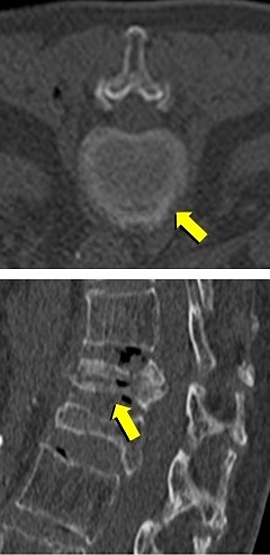

◆圧迫骨折/骨転移に対する経皮的椎体形成術(PVP)

経皮的椎体形成術(骨セメント)の実際

局所麻酔下で皮膚から椎体に針を刺し、骨セメントを注入することにより、椎体を内部

から固定する方法です。骨粗鬆症による圧迫骨折で痛みを伴うもの、椎体の腫瘍(癌の

転移など)による痛みを伴うものが適応となります。古い圧迫骨折による亀背や側弯が

あっても、痛みがないものや、症状のないものは治療の適応となりません。症状が軽度

であっても歩行時、起立時に痛みがあり、画像診断で治癒していない圧迫骨折がある場

合は治療の適応となります。術前の画像診断にはMRI検査が重要で、病的骨折、骨粗鬆

症性骨折、治癒していない骨折の診断に不可欠です。

治 療 前 セメント注入中 治 療 後

当院では各種の透視画像下に椎体形成術を行っています。患者様は画像装置台に腹臥位

になって頂きます。皮膚に局所麻酔をして、透視下に針を骨折している椎体前方に挿入

します。骨セメント(時間がたてば硬化する液体)を注射器にて椎体内にゆっくりと透

視で観察しながら注入します。手術時間は一つの椎体であれば30〜60分程度です。セ

メントにより背骨が補強され、痛みを緩和することができます。除痛効果は速効性で、

注入直後より歩行可能となる場合も少なくなく、大半が24時間以内に痛みが良くなり

ます。通常入院期間は1〜2日です。この術式に関してご質問等がありましたら、外来

で御相談下さい。